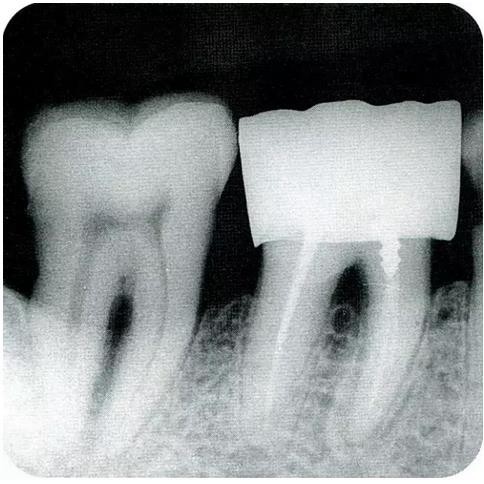

▼圖6-1 下頜第一后磨牙的頰舌間存在III度的根分叉病變,預(yù)在進行牙根分割后保留遠(yuǎn)中根。

▼圖6-2 中下頜第一后磨牙雖然切除了一半,但是遠(yuǎn)中根也有2根分根,所以不得已拔除(被拔除遠(yuǎn)中根的近中面觀察)。